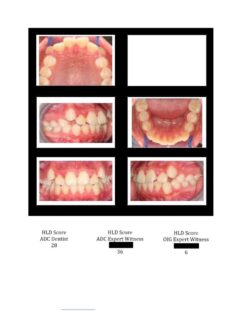

So here again are photos of children’s teeth that were pre-approved for treatment by the state’s Medicaid claims administrator TMHP/ACS, that HHSC-OIG now claims were fraudulently scored by Medicaid dental providers. These cases are from the SOAH hearings that have been completed for Harlingen Family Dentistry and Antoine Dental Center. The SOAH courts found both practices innocent of any allegation of Medicaid fraud or misrepresentation. The photo pages show the attending dentist’s HLD score, the dentist’s expert witness score and the OIG expert’s score.

Antoine Dental Center